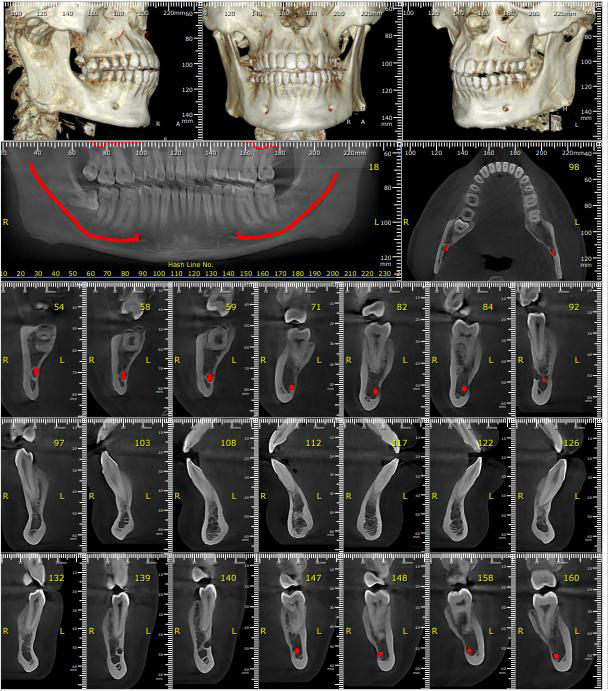

On examination, we found:

- Deep bite and restricted jaw movement

- Severe muscle tenderness (masseter, temporalis, pterygoid)

- Jaw deviation with function

- MRI confirmed his TMJ dysfunction